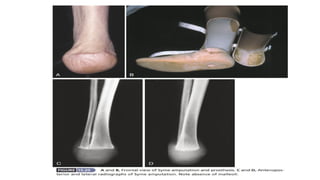

SYME’S AMPUTATION

• A classical ankle amputation.

• Removal of the foot with calcaneum and cutting of tibia and fibula just above the

ankle joint with retaining heel flap

• produces a durable weight-bearing stump.

• Used in trauma (crush injury), congenital deformities of foot wherein amputation is

inevitable, nonischaemic damage of foot and malignancies in distal part of the foot.

• Special value to patients who do not have access to modern artificial limbs.

• The end of the stump is at a height of about 6–8 cm from the ground and may be

walked on without a prosthesis

COMMONLY USED PROSTHESIS

Syme's amputation - Elephant boot,Canadian Syme's prosthesis.